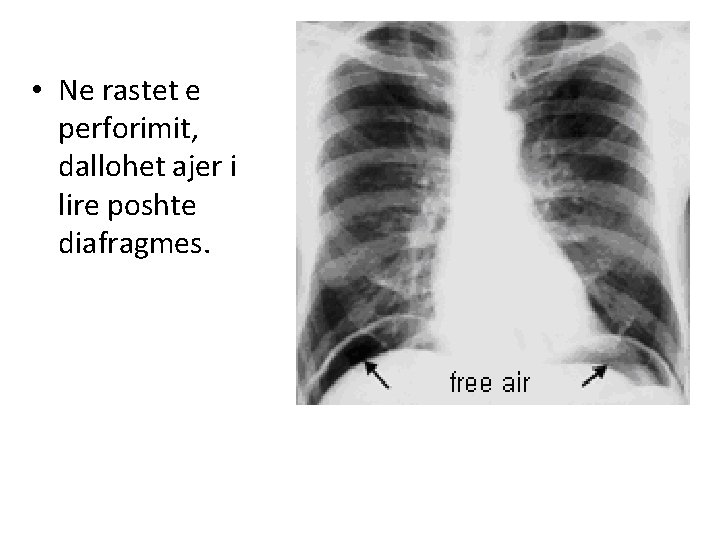

• Ne rastet e perforimit, dallohet ajer i lire poshte diafragmes.